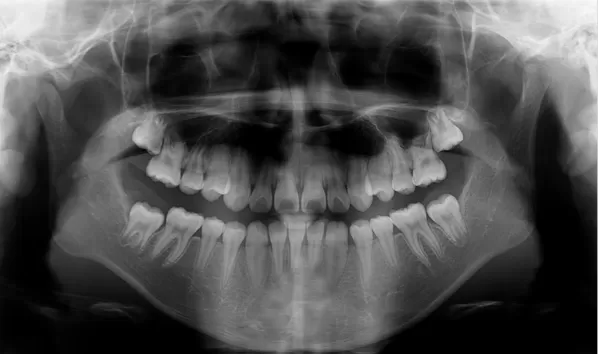

X-rays before treatment

[Panoramic Radiography/Lateral Cephalogram]